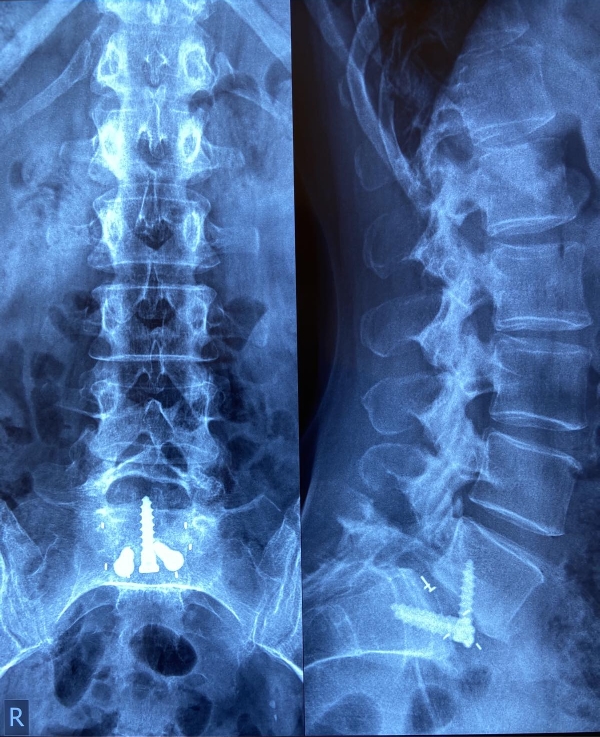

Αυτή η περίπτωση είναι ιδανική για διενέργεια πρόσθιας διασωματικής σπονδυλοδεσίας, η οποία και διενεργήθηκε με τη χρήση ευρέως κλωβού και μίξη αυτομοσχεύματος από το λαγόνιο (μέσω της ίδιας τομής) και DBM. Σταθεροποίηση με τρεις βίδες με πολύ καλή συγκράτηση και συμπίεση του κλωβού. Ακολουθούν οι μετεγχειρητικές ακτινογραφίες.